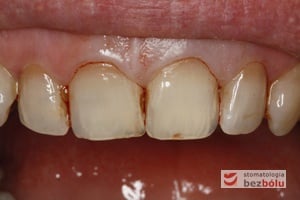

Pacjentka lat 37 zgłosiła się z silnymi dolegliwościami bólowymi siekacza centralnego na górze po stronie lewej. Ząb był w trakcie leczenia kanałowego w innej placówce. Jedno wizytowe leczenie kanałowe polegało na starannej instrumentacji kanału korzeniowego oraz wypłukaniu podchlorynem sodu, a następnie starannym odtłuszczeniu i wysuszeniu systemu korzeniowego. Kanał został szczelnie zamknięty metodą termokondensacji ciśnieniowej przy pomocy instrumentarium, tj. system B i Obtura. Kontrola radiologiczna potwierdziła szczelność wypełnienia oraz ujawniła obecność kanałów bocznych, które bez starannego wypełnienia mogłyby stać się przyczyną infekcji w obrębie wyrostka zębodołowego. Wypełnione kanały boczne przypominały dymiące fabryczne kominy. Leczenie zostało zakończone odbudowaniem zrębu koronowego z udziałem ćwieka z włókna szklanego, który został otulony materiałem kompozytowym nanohybrydowym. Jedno wizytowe sprawne leczenie endodontyczne przyniosło pacjentce natychmiastową ulgę, a odbudowa korony zredukowała ryzyko złamania zęba.